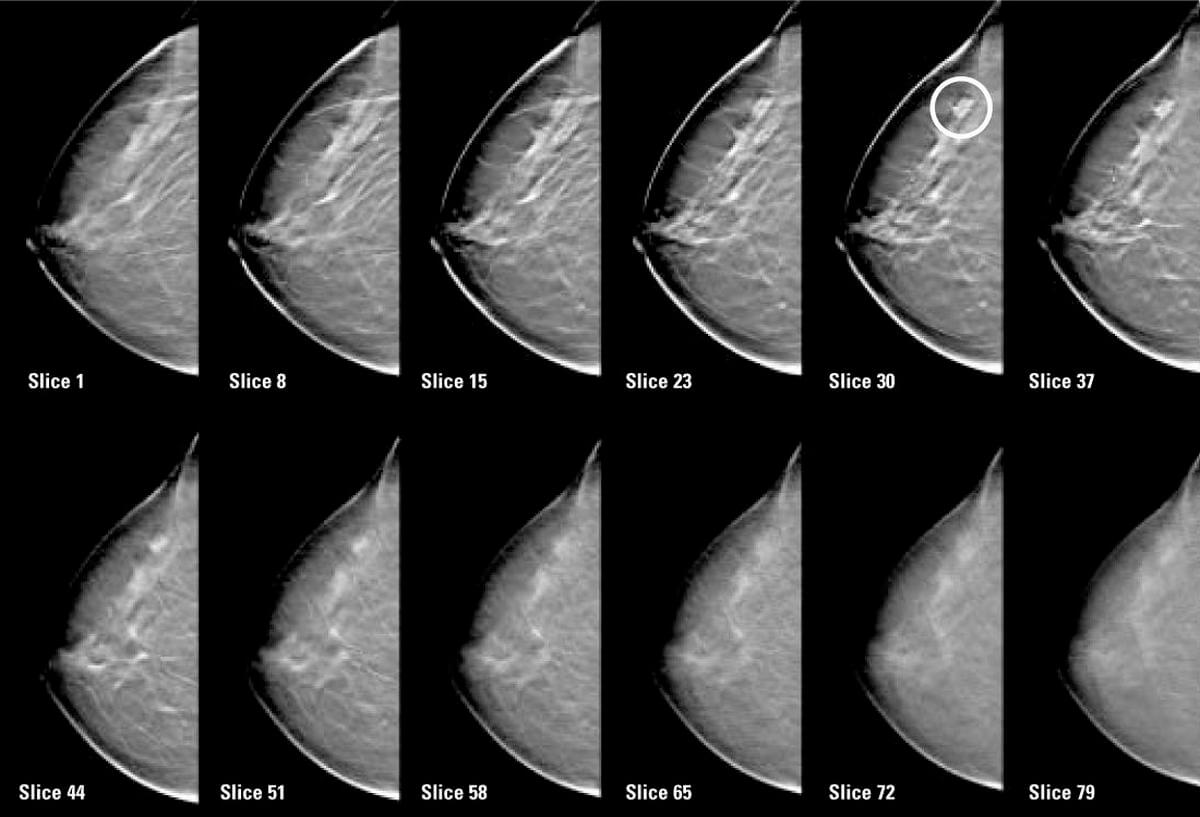

В процессе томосинтеза молочной железы низкодозовые рентгеновские лучи под разными углами осуществляют последовательные, послойные томограммы на заданной глубине и с фиксированным расстоянием между каждым срезом. В результате получается серия снимков (от 11 до 25), каждый из которых отображает определенный слой железисто-фиброзной ткани.

Рис. 4. Послойные томограммы молочных желез при исследовании методом томосинтеза.

Цифровой детектор передает изображения срезов на рабочую станцию врача, где при помощи специальных программ генерируются послойные цифровые снимки, которые максимально точно отражают состояние тканей молочных желез. Послойное сканирование позволяет с большей точностью оценить локализацию образования, его форму и размеры.